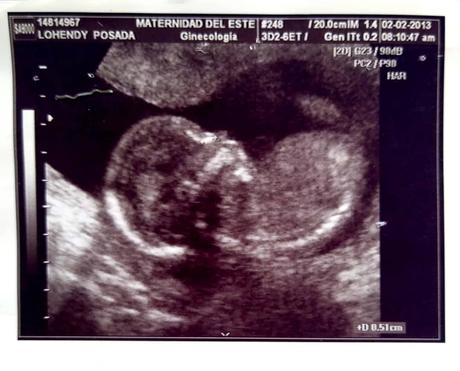

Ayer te fuiste formando y ya no solo te llevaba en mi sangre sino que ya tenías la forma como un grano de mostaza y luego de un fréjol con pequeños latidos que confortaban mi alma y mi corazón.